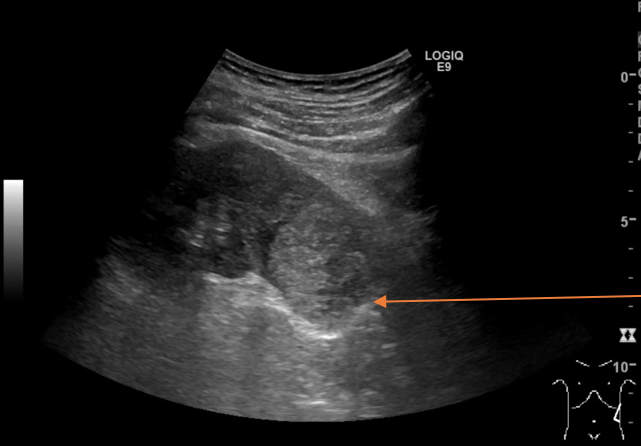

Renal Cell Carcinoma Ultrasound Images Renal Cell Carcinoma Ultrasound Images Van Hoge Kwaliteit

Gedetailleerde renal cell carcinoma ultrasound images tonen tumorkarakteristieken voor nauwkeurige diagnose en evaluatie van nierkanker.

Renal Cell Carcinoma Radiology Case Renal Cell Carcinoma Radiology Case Kenmerken

In dit renal cell carcinoma radiology case worden de beeldvorming en typische kenmerken van deze nierkanker duidelijk beschreven.